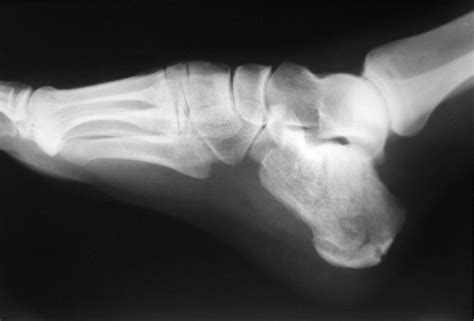

A Calcaneus X Ray is a medical imaging technique used to visualize the calcaneus, or heel bone. This type of X-ray is particularly useful for diagnosing fractures, dislocations, and other abnormalities in the heel area. The calcaneus is the largest bone in the foot and is subject to significant stress and impact, making it prone to injuries, especially in athletes and individuals involved in high-impact activities.

Interpreting the results of a Calcaneus X Ray requires the expertise of a radiologist or orthopedic specialist. The images are carefully examined for signs of fractures, dislocations, or other abnormalities. Here are some common findings that may be identified:

• Bone Spurs: These are bony projections that can form on the heel bone due to chronic stress or inflammation. Bone spurs can cause pain and discomfort, especially during weight-bearing activities.

• Arthritis: X-rays can also reveal signs of arthritis, such as joint space narrowing and bone spurs, which can affect the heel and surrounding joints.

• Calcaneal Fractures: These are fractures of the heel bone and can occur due to falls, high-impact activities, or trauma. They are often classified as intra-articular (involving the joint) or extra-articular (not involving the joint).

• Heel Spurs: These are bony projections that can form on the underside of the heel bone. They are often associated with plantar fasciitis and can cause significant pain and discomfort.